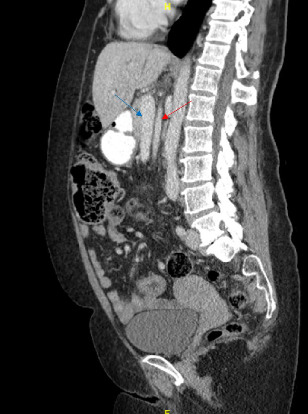

Abstract Image